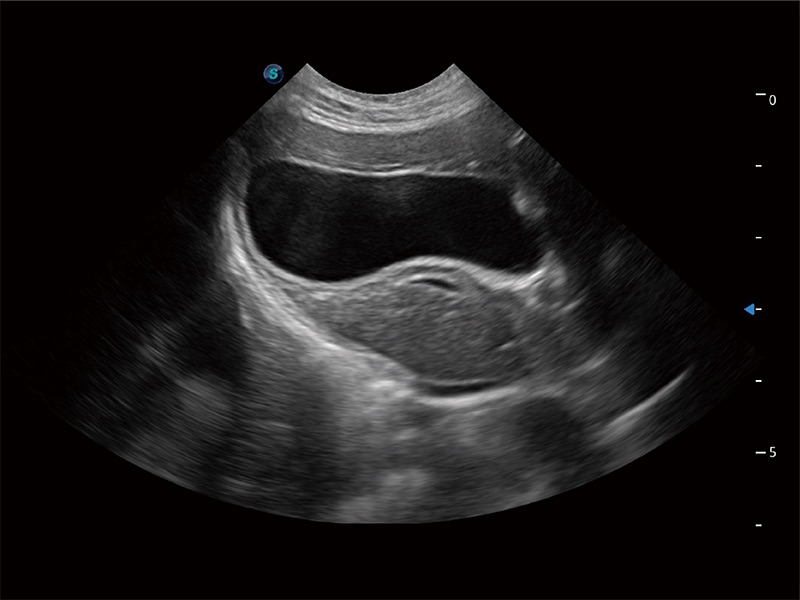

一鍵自動識別膀胱壁及自動測量膀胱容積,不受膀胱形狀和大小的限制,幫助醫(yī)生快速精準(zhǔn)獲得測量的數(shù)據(jù)。

ProPet 80 全新的動物超聲智能軟件和豐富的探頭群,為動物醫(yī)生提供了高清晰度和精細(xì)分辨率的圖像,無論在寵物、馬科、畜牧還是實(shí)驗(yàn)室動物等應(yīng)用中都可以輕松應(yīng)對,為您的日常工作帶來滿意的體驗(yàn)。